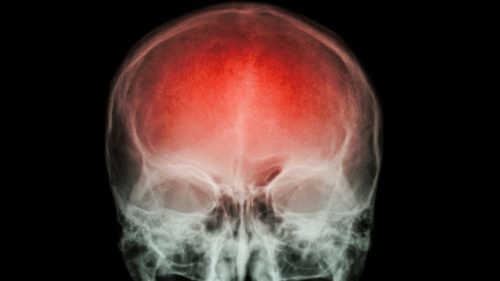

O acidente vascular cerebral (AVC) é uma emergência médica que pode mudar a vida de uma pessoa em questão de minutos. Ele ocorre quando o fluxo sanguíneo para uma parte do cérebro é interrompido ou reduzido, causando a morte de milhões de neurônios por falta de oxigênio e nutrientes. Em um AVC, cada minuto conta: podem morrer até 1,9 milhão de células cerebrais por minuto, por isso a detecção precoce e o atendimento médico imediato são determinantes para evitar sequelas graves ou até mesmo a morte.

Os avanços tecnológicos em imagens diagnósticas, como tomografia computadorizada, ressonância magnética e angiografia, permitem que os profissionais de saúde visualizem em detalhes as áreas afetadas do cérebro, identifiquem o tipo de AVC e tomem decisões clínicas em questão de minutos. Graças a essas inovações, os médicos podem iniciar tratamentos mais rápidos e eficazes, melhorando as chances de recuperação dos pacientes. Fonte: Artigo Siemens Healthineers.